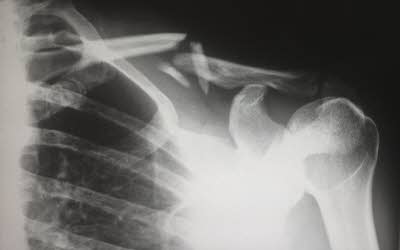

흉부X선 검사 실시 후 결핵의심자에 한하여 확진검사 실시합니다.